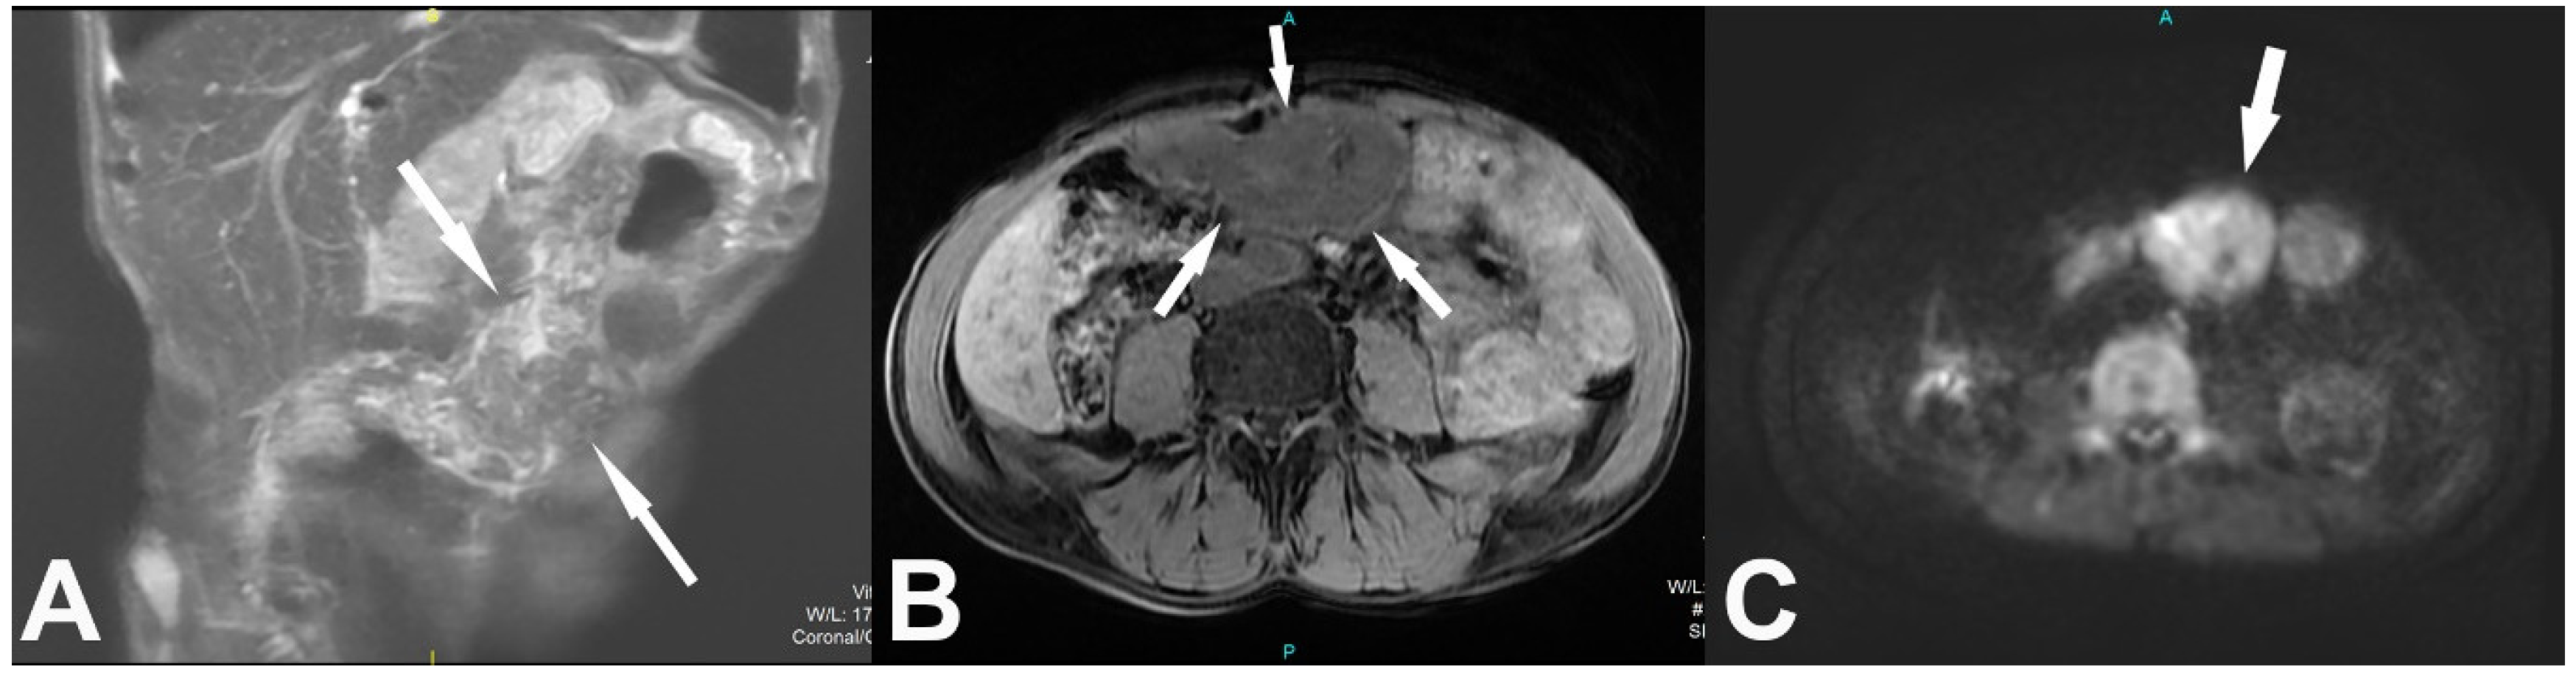

2. Case Report